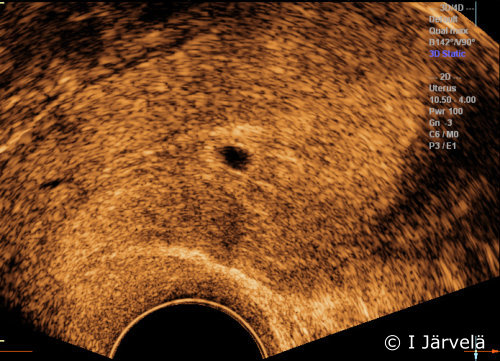

Incipient miscarriage. Incipient miscarriage in pregnancy week 5+4. Note: yolk sac cannot be detected (cf. pictures Pregnancy Week 5 (Ultrasound Scan) Pregnancy Week 6 (Ultrasound Scan)).

Pictures: Ilkka Järvelä; text: Dimitrios Scordas